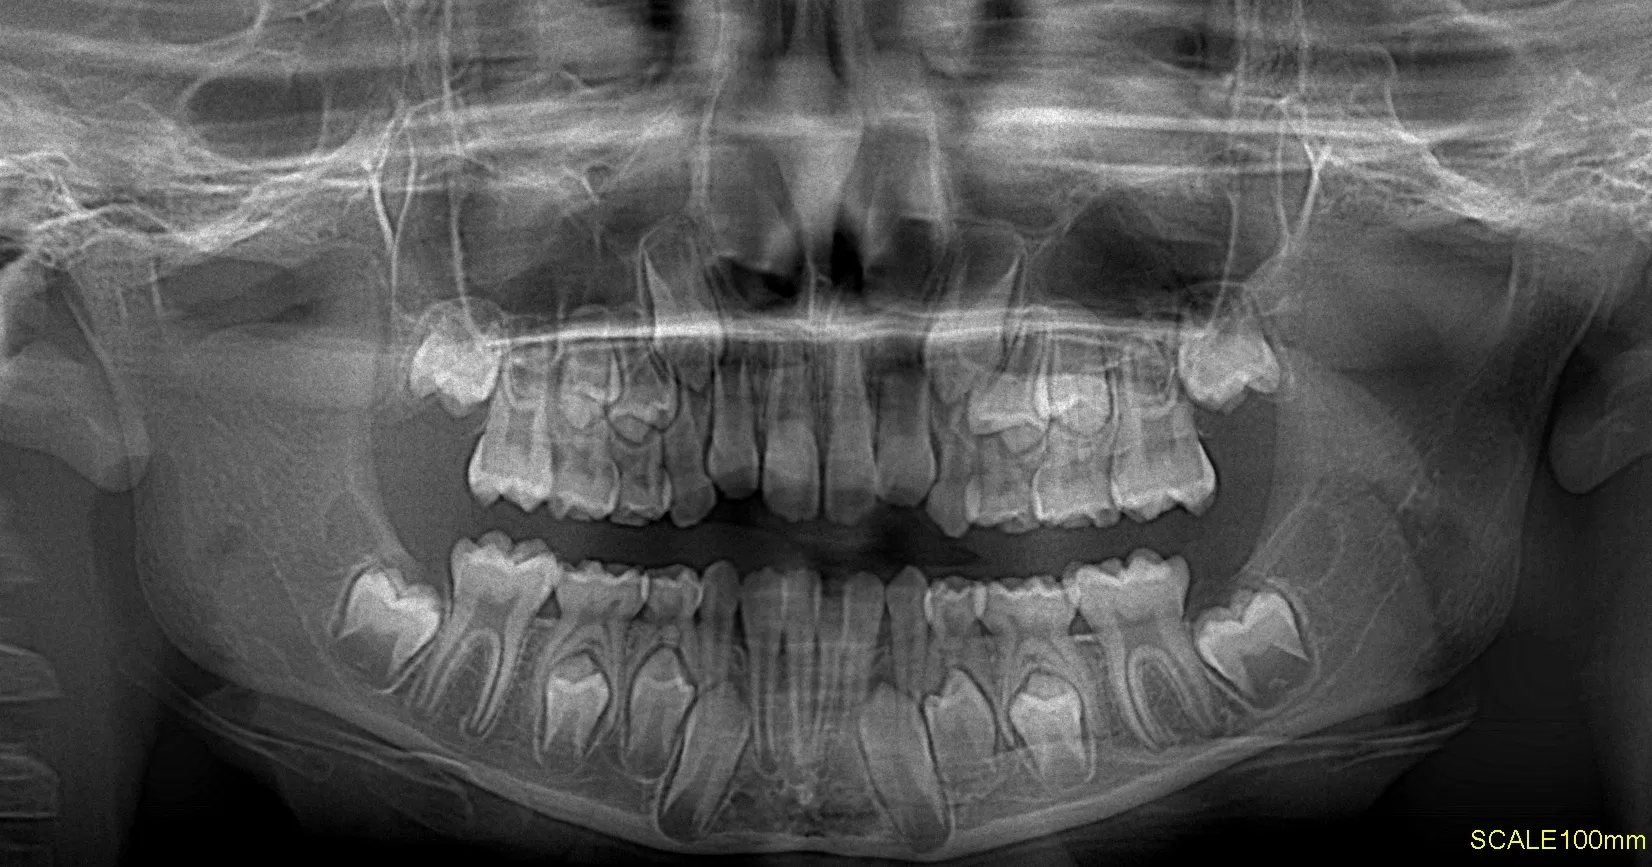

Las radiografías extraorales permiten obtener imágenes completas de los maxilares, la articulación temporomandibular (ATM) y las estructuras faciales sin colocar el sensor dentro de la boca.

Realizamos estudios como radiografía panorámica, cefalométrica, de senos paranasales y de ATM, esenciales para tratamientos de ortodoncia, cirugía y diagnóstico integral.